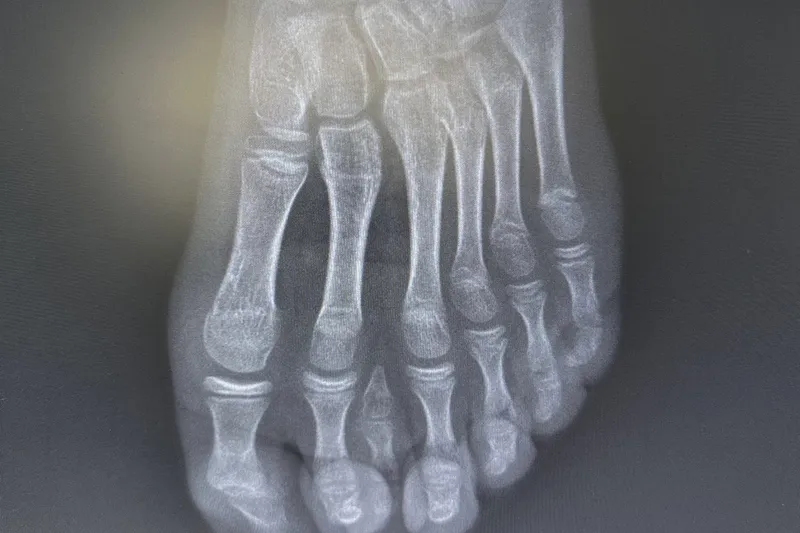

Batman'da nadir 7 parmaklı ayak vakası başarıyla tedavi edildi

Batman Eğitim ve Araştırma Hastanesinde, 8 yaşındaki E.H. isimli hastada nadir görülen doğumsal bir ayak anomalisi başarıyla tedavi edildi.

Yetkililer, el ve ayaklarda fazla (polidaktili) ya da eksik parmak vakalarına zaman zaman rastlandığını ancak 7 parmaklı ayak olgularının oldukça nadir görüldüğünü belirtti.

Genel yaklaşımda bu tür vakalarda cerrahi planlamanın ayağın beş parmaklı anatomik yapısına uygun şekilde yapıldığı ifade edildi. Ancak hastanın yapılan detaylı klinik ve radyolojik değerlendirmelerinde altı parmağın; falanks (parmak kemikleri), metatars (tarak kemikleri) ve diğer ayak kemikleri ile uyumlu ve düzgün şekilde geliştiği tespit edildi.

Uzmanlar, mevcut altı parmağa müdahale edilmesinin ayak biyomekaniğini ve dengesini olumsuz etkileyebileceğini değerlendirdi.

Bu doğrultuda cerrahi planlama yeniden yapılarak, fonksiyonel açıdan yetersiz ve estetik olarak problem oluşturan tek parmağın çıkarılmasına karar verildi. Operasyon sırasında diğer parmaklara ait damar ve sinir yapıları titizlikle korunurken, mikrocerrahi teknikler kullanılarak işlem sorunsuz şekilde tamamlandı.

Operasyon, Batman Eğitim ve Araştırma Hastanesinde görevli Ortopedi ve Travmatoloji Uzmanı Uzm. Dr. Mehmet Yavuz Başer tarafından başarıyla gerçekleştirildi. Hastanın genel durumunun iyi olduğu ve operasyonun başarılı şekilde sonuçlandığı bildirildi.

Hastane yönetimi tarafından yapılan açıklamada, gerçekleştirilen bu özellikli cerrahi müdahalenin ileri cerrahi teknikler, mikrocerrahi hassasiyet ve bireye özgü planlamanın bir arada uygulanmasıyla mümkün olduğu vurgulandı.